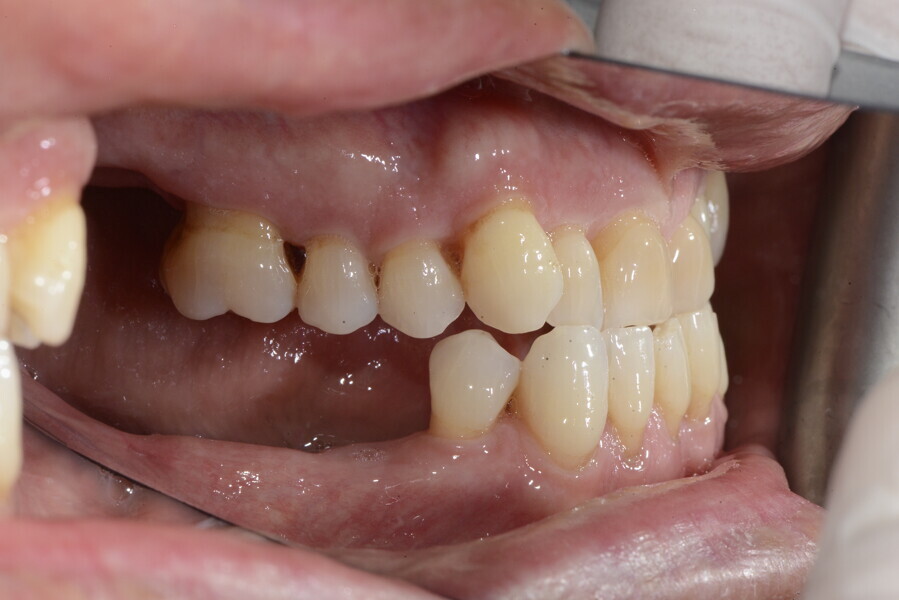

The 58-year-old patient wished to improve his oral aesthetics and function, complaining of mobility of the posterior teeth and wear of the anterior teeth. After data collection, a very complex situation was identified (Figs. 11–13):

1. severe periodontitis with poor prognosis of some teeth;

2. anterior crossbite;

3. severe wear mainly of the anterior teeth and compensatory eruption;38

4. atypical swallowing and lower posture of the tongue at rest;

5. masticatory dysfunction during the mastication test; and

6. no significant signs of temporomandibular disorder.